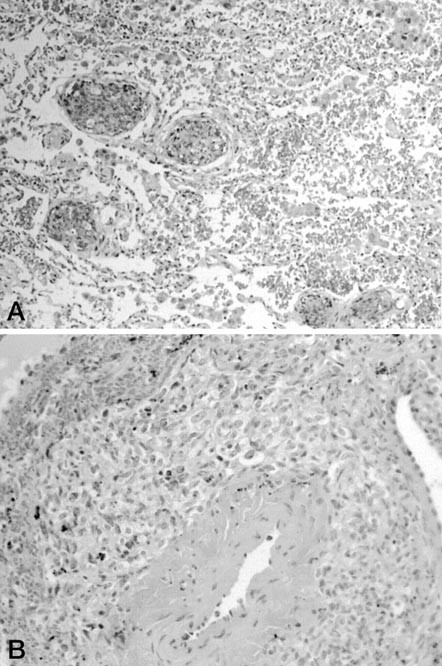

The primary histologic features and immunohistochemical staining results of the cases are presented in Table 2. In all cases, tumor foci were peripheral, multiple, and generally formed nodules. Peripheral lung septae or the subpleural interstitium were involved in all cases (Fig. 1). Tumor extended into surrounding pulmonary alveoli to varying degrees. Lymphangitic spread, when present, usually, but not exclusively, involved septal lymphatics and vessels (Fig. 4A). Circumferential growth around small vessels and bronchioles was noted in seven cases (32%; Fig. 4B). This growth pattern often resulted in tumor thrombi or bronchiole obstruction when tumor penetrated through the walls of the structure. Vasoformative regions were identified in 15 cases (71%). These regions consisted of anastomosing channels lined by mildly to markedly atypical tumor cells. These channels often contained red blood cells (Figs. 3, A–B, and 5A). Solid growth occurred in 17 cases (77%; Fig. 2). Fresh hemorrhage, clusters of siderophages, and extracellular hemosiderin deposition occurred both within tumor nodules and in immediately adjacent lung parenchyma (Fig. 5B).

Cytologically, the tumor cells were either spindle or round to polygonal (epithelioid) in shape (Fig. 6, A–B). Ten cases contained a mix of spindled and epithelioid cells. Nine cases were exclusively composed of spindle cells, and two cases were composed of epithelioid cells only. The nuclear to cytoplasmic ratio ranged from generally low in spindle cells to progressively higher for high-grade epithelioid cells. The cytoplasm was lightly eosinophilic, and intracytoplasmic lumina consistent with incipient vessel development was rare (Fig. 6A). Although five cases disclosed areas of minimal nuclear atypia consisting of small, oval nuclei with mild nuclear hyperchromaticity, all cases had at least one focus of higher grade tumor comprising cells with moderate to severe nuclear pleomorphism (including multilobulation, marked hyperchromaticity, coarse chromatin, and irregular nuclear borders with sharp-angled notching). High grade epithelioid cells commonly contained large, vesicular nuclei with macronucleoli (Fig. 6B). Multinucleated tumor giant cells were identified in several cases. Mitotic figures were typically easy to find, and high-grade foci contained cells with atypical division figures.